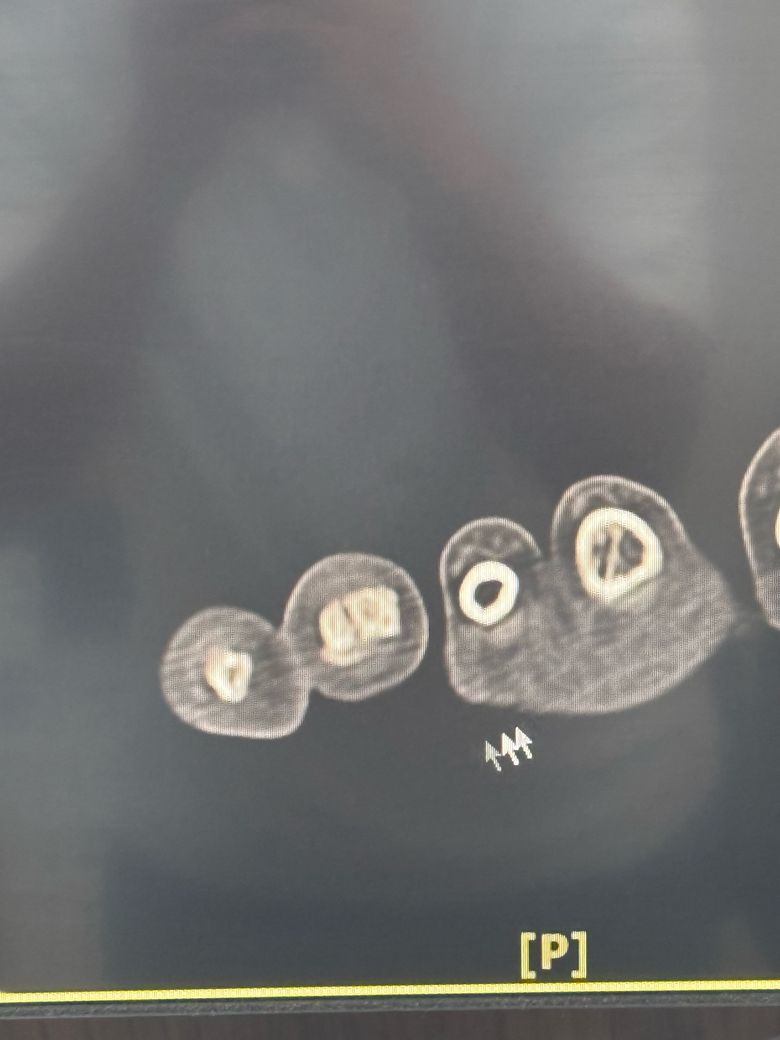

• 3번 째 사진

안타깝지만 해당 컷 사진 몇장만으로는 정확한 상태 파악 및 수술치료 여부 확인 불가능하며, CT 찍으신 정형외과 진료 시 자세히 여쭤보시는게 더 좋겠습니다.

이미지상 발가라 뼈에 금이 가거나 골절 소견이 있어보이지만 정확한 수술 여부는 골절의 위치 각도 뼈 어긋남 여부에 따라 다릅니다.